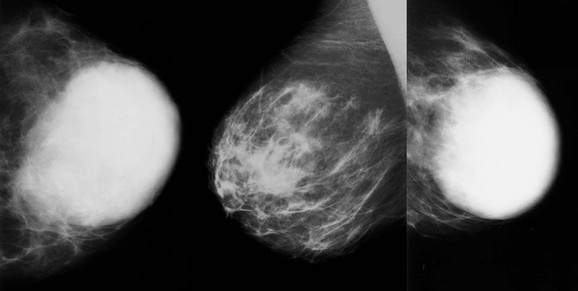

Medullary carcinoma is a very rapidly growing cancer that typically presents as a palpable mass in young or middle-aged women (Fig. 11-6). The median age of diagnosis is 51. “Medulla” means marrow. Like basal cell (triple negative) IDC, medullary carcinoma is characterized by a brisk lymphocytic response, absence of fibroglandular differentiation, and pleomorphic nuclei. There is usually little or no associated DCIS. So at first glance under the microscope medullary carcinoma resembles an aggressive IDC. There is considerable interobserver variability in the pathologic diagnosis of medullary carcinoma that may explain the variable patient outcomes reported across different series. The prognosis for women with this cancer is better than for typical IDC in most series.

FIGURE 11-6 Medullary Carcinoma.

This 44-year-old woman presented with a palpable mass (triangle) that corresponds to an oval, relatively circumscribed, high-density mass. US demonstrates a hypoechoic, solid, oval mass with posterior acoustic shadowing.

On mammography, medullary carcinoma typically presents as a round or oval, circumscribed mass without calcifications. It is often palpable.

Mucinous (colloid) carcinoma is characterized by tumor cells floating in a pool of mucin (Fig. 11-7). This lesion presents most commonly in older women with a median age of 71. Your last experience with an upper respiratory infection should remind you that mucin is a soft semiliquid. As a result, the mammographic appearance is usually a low-density mass rather than a dense clump of cells like most cancers (Fig. 11-8). The margins are typically fairly well-circumscribed. The US appearance can be relatively isoechoic, and often there is posterior acoustic enhancement. Like proliferative fibroadenomas, these masses are very T2 hyperintense on MRI, but tend to be more heterogeneous on T1 postcontrast sequences.

FIGURE 11-8 Mucinous Carcinoma.

A 67-year-old woman with a round mass with ill-defined margins in the left breast at 1 o’clock. On US, there is an isoechoic lobular mass with abrupt defined margins.